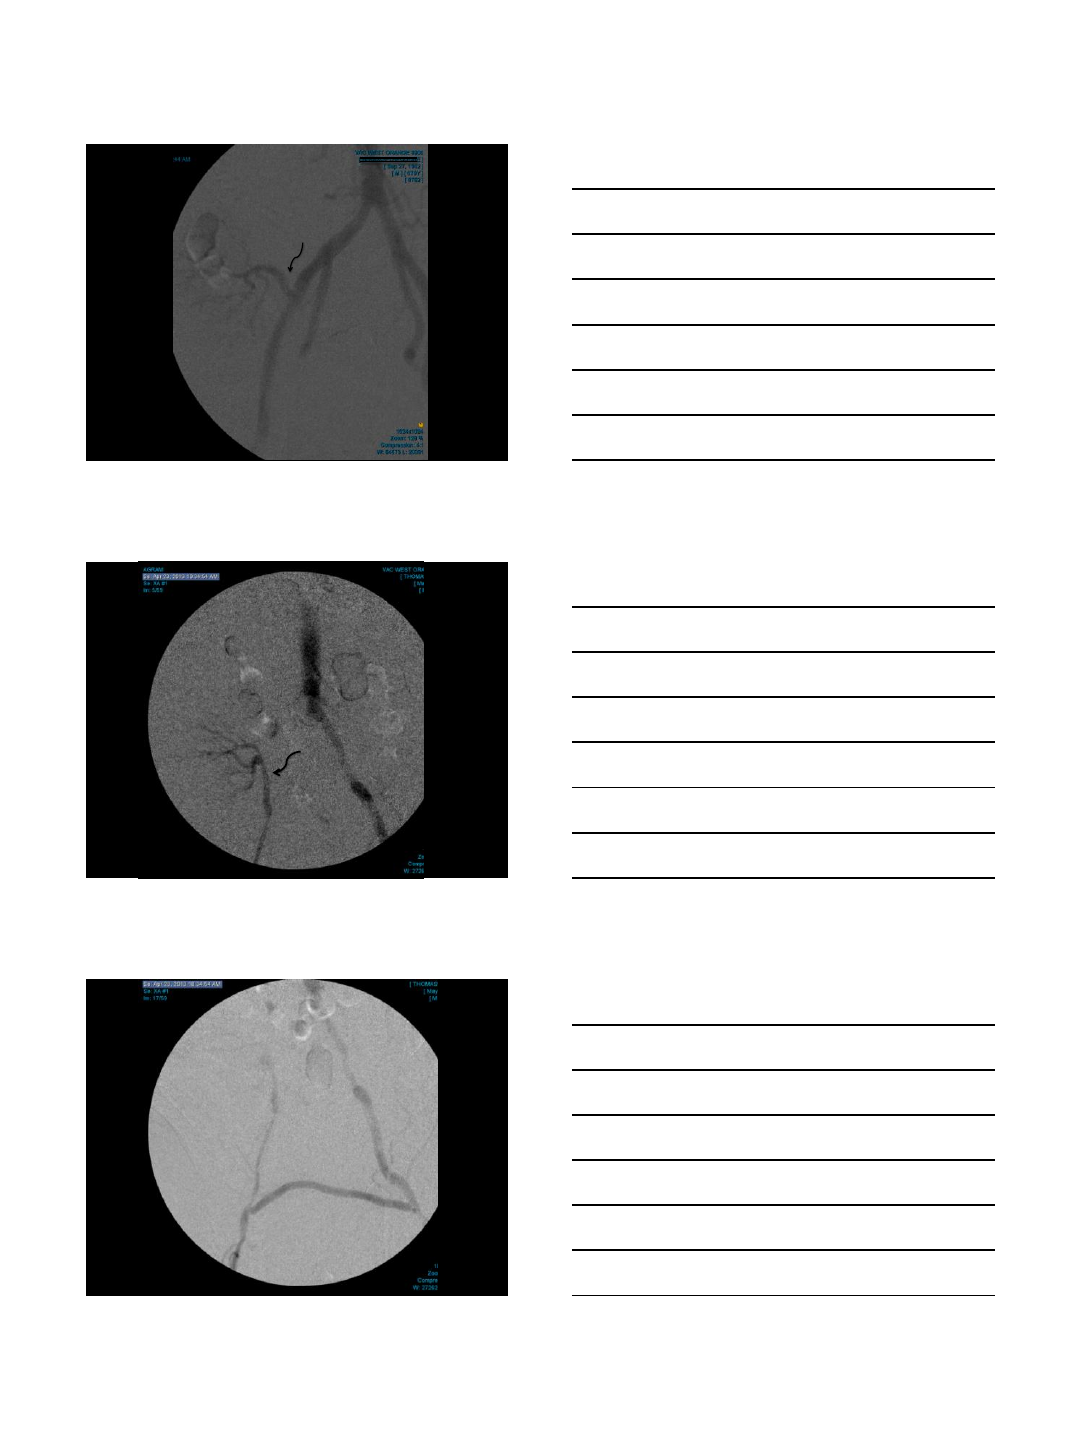

DIALYSIS ACCESS INTERVENTION

Case Presentation

•68 year old woman with ESRD

•On hemodialysis via an AV fistula

•Allergic to iodinated contrast

•Refractory to pre-medication

•Ongoing problems with her AV fistula

•Bleeding post-dialysis

•Requires 3 month-surveys

CO2 Fistulogram

•This patient’s procedures are

completed whenever necessary without

the use of contrast medium

•No further allergic reactions